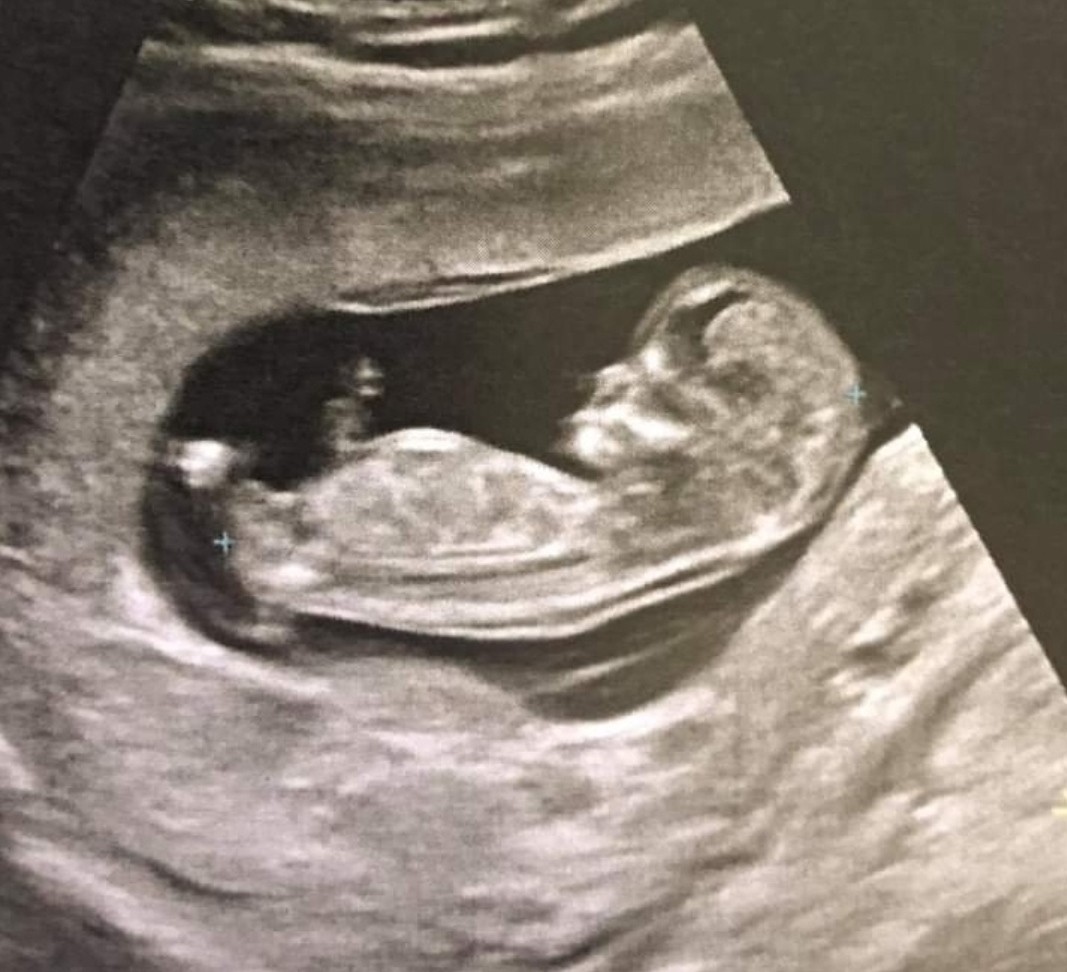

Już jestem jest wszystko ok :) dalej dziecko większe o 2 tyg i termin na listopad już się oficjalnie przesuną, trochę mnie zestresowała tylko informacja że może to być chłopiec, a mam dużą nadzieję na kolejną dziewczynkę bo z chłopcem mam wrażenie że nie dam sobie rady

Jakoś wizualizowalam sobie zawsze 3 dziewczynki

• IMG_20220427_205312.jpg

IMG_20220427_205312.jpg

158,5 KB · Wyświetleń: 105